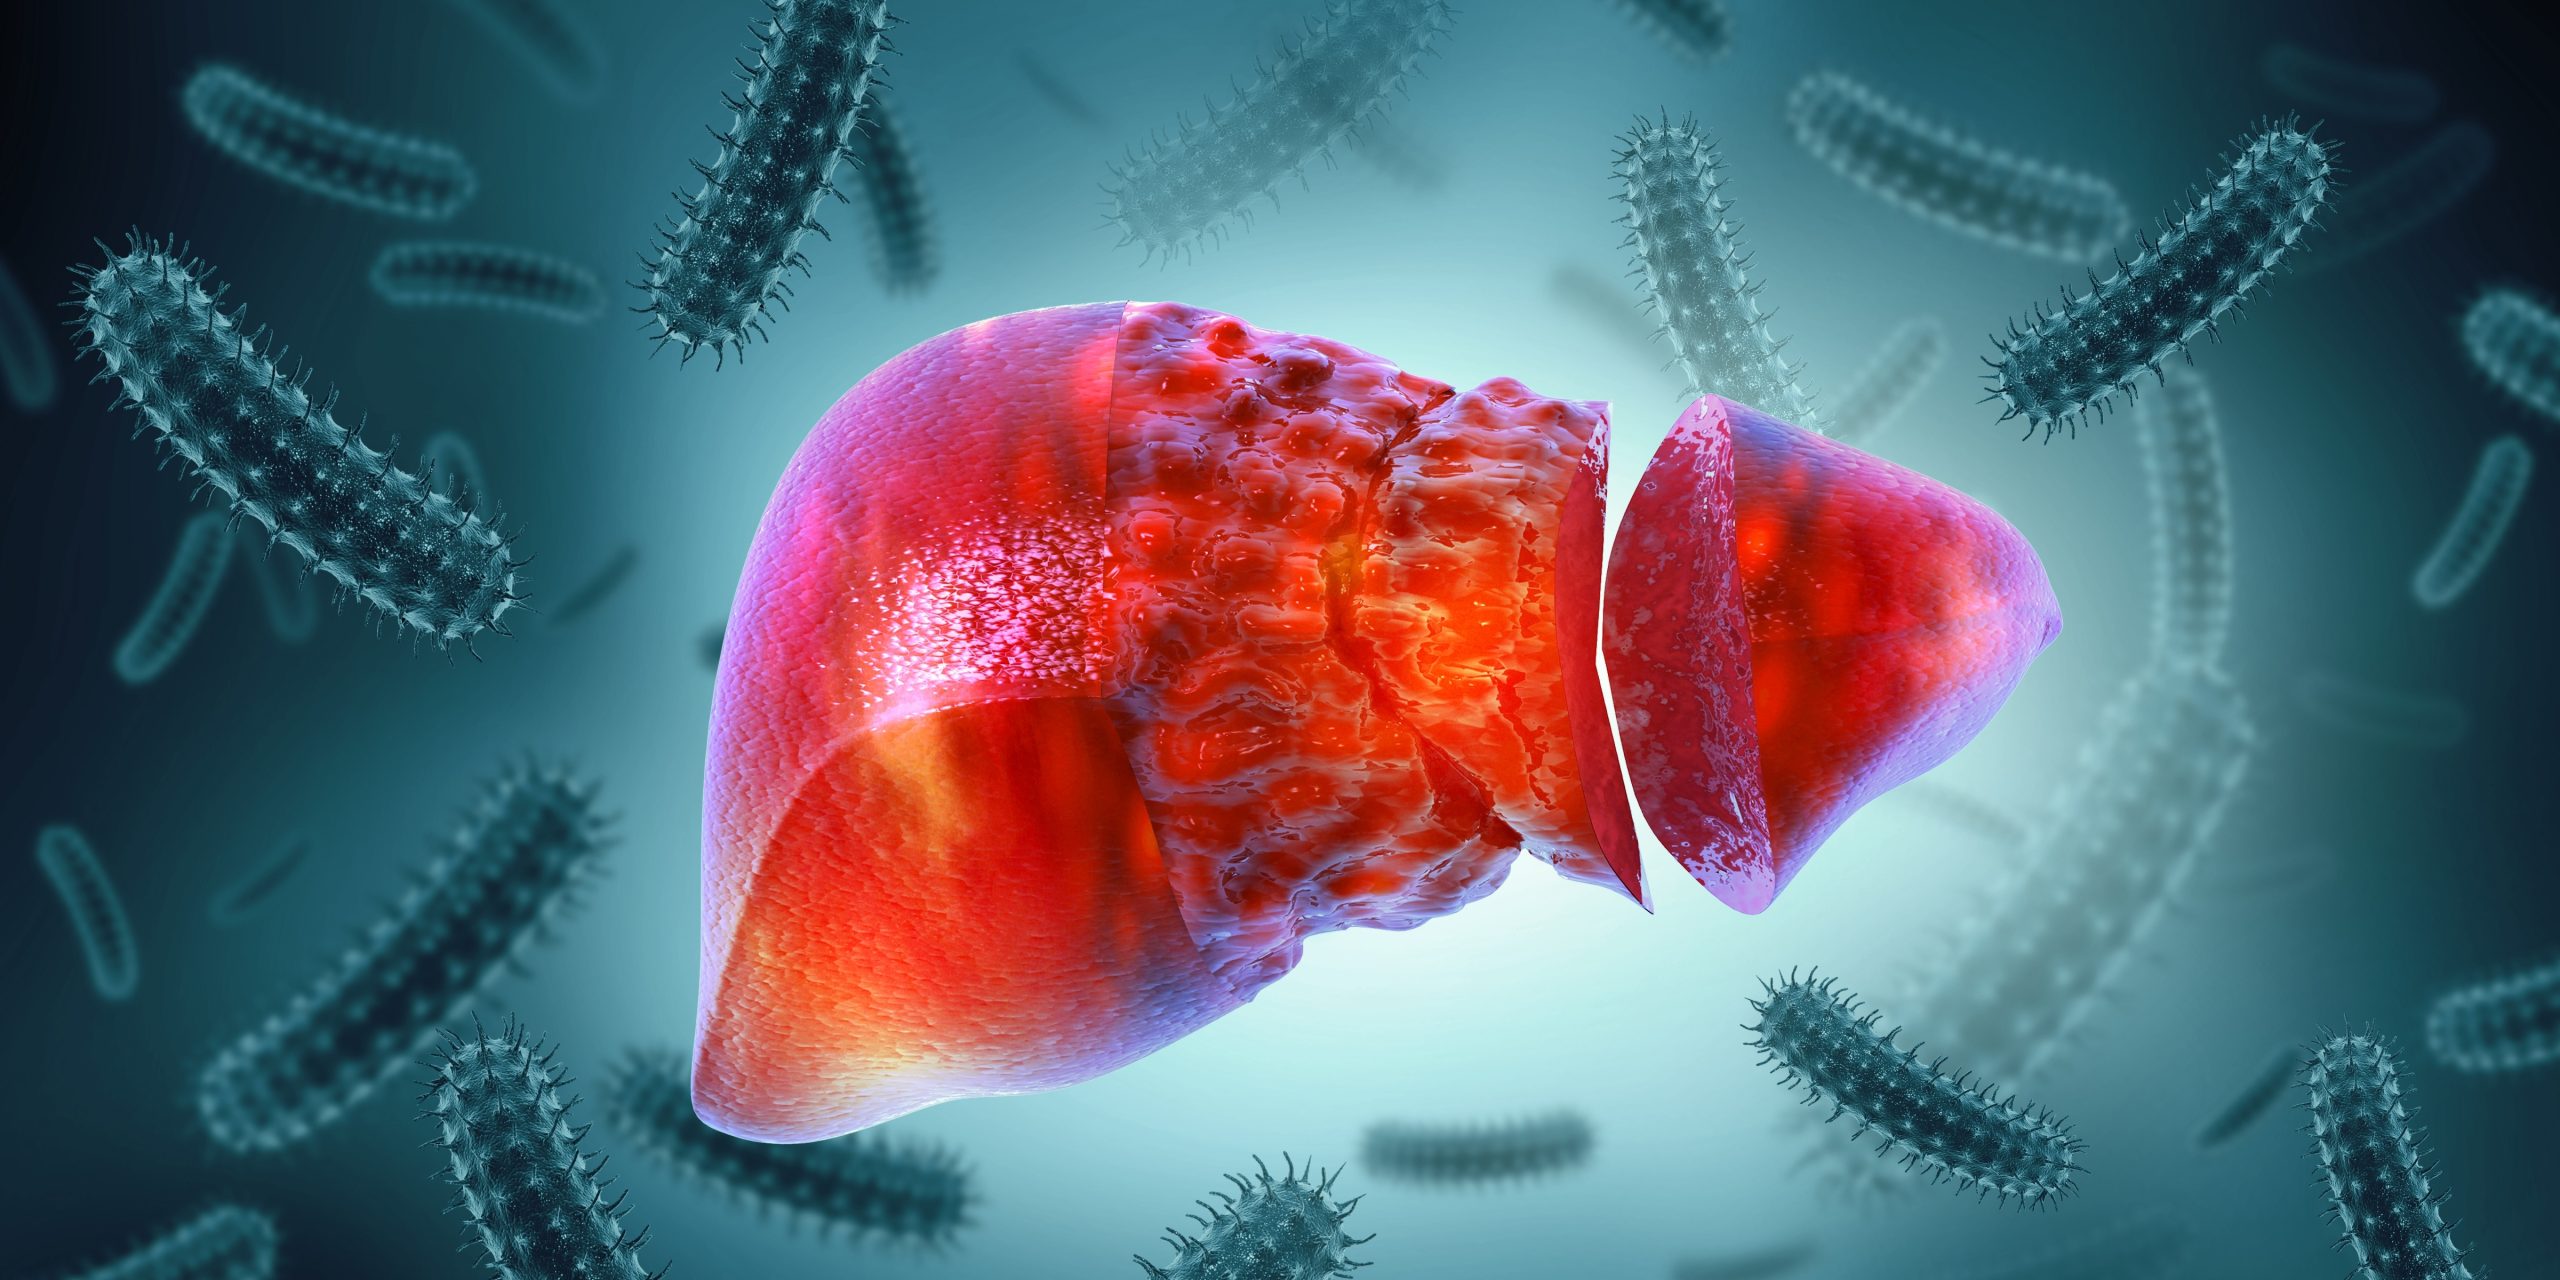

Scientists have developed a 3D liver model, known as the periportal assembloid. This model replicates the liver’s complex structure and bile transport system, enabling more precise study of disease progression.